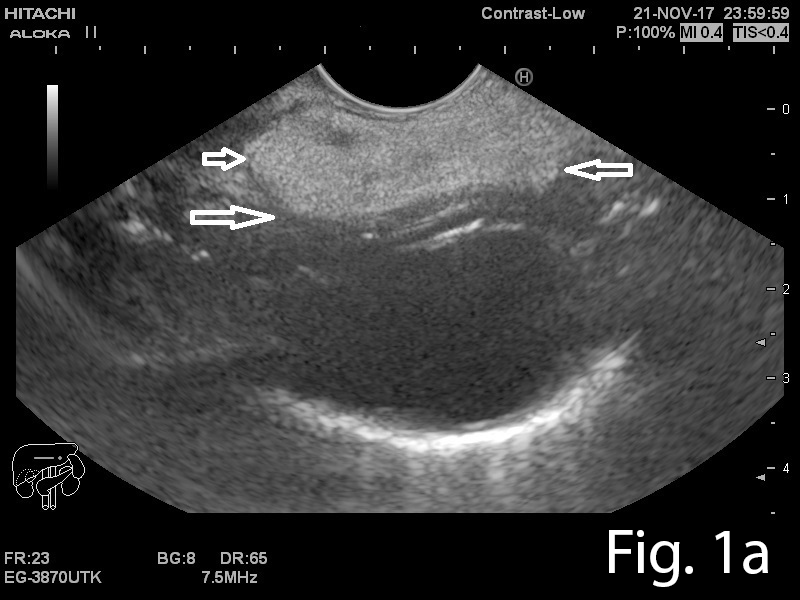

A 46-year old man presented to the gastrointestinal clinic complaining of dysphagia, regurgitation and a sensation of a lump in the throat, symptoms which had progressively worsened over the previous year. Upper GI endoscopy revealed a giant soft mass within the esophageal lumen, with a smooth surface covering, originating from the cervical esophagus, with a positive ”squeeze sign” (Video 1). EUS was performed and showed a giant mobile lesion occupying the esophageal lumen, with hyperechogenic structure, suggestive of a lipoma (Figure 1ab). Contrast-enhanced EUS did not depict any signals inside the subepithelial mass in the early arterial or late venous phases(Figure 1c). In order to define the surgical approach, a CT of the neck, thorax and abdomen was performed and it revealed the submucosal pedunculated tumor mass, confirming the diagnosis of lipoma (Figure 2).

Figure 1a-b. EUS showing a hyperechogenic lesion with a smooth margin arising from the submucosal layer of the esophagus. 1c. Contrast-enhanced EUS indicated completely absent signals, for both the early arterial and late venous phases.